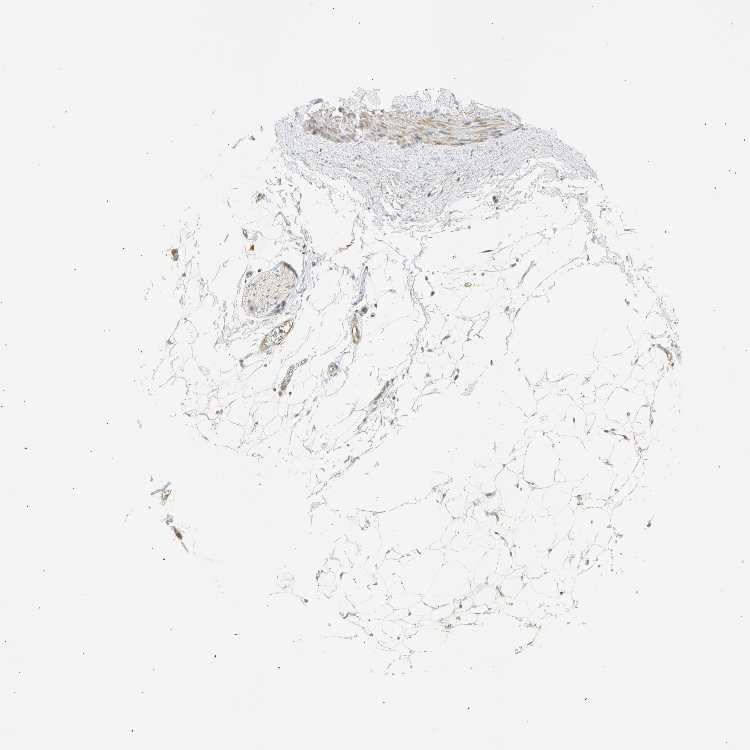

SOFT TISSUE 1 - Antibody stainingi

Antibody staining in the annotated cell types in the current human tissue is reported as not detected, low, medium, or high, based on conventional immunohistochemistry profiling in selected tissues. This score is based on the combination of the staining intensity and fraction of stained cells.

Each image is clickable and will lead to virtual microscopy that enables deeper exploration of all samples and also displays staining intensity scores, fraction scores and subcellular localization as well as patient and tissue information for each sample.

Antibody HPA011420

Chondrocytes Not detected

Fibroblasts Low

Peripheral nerve Medium

SOFT TISSUE 2 - Antibody stainingi